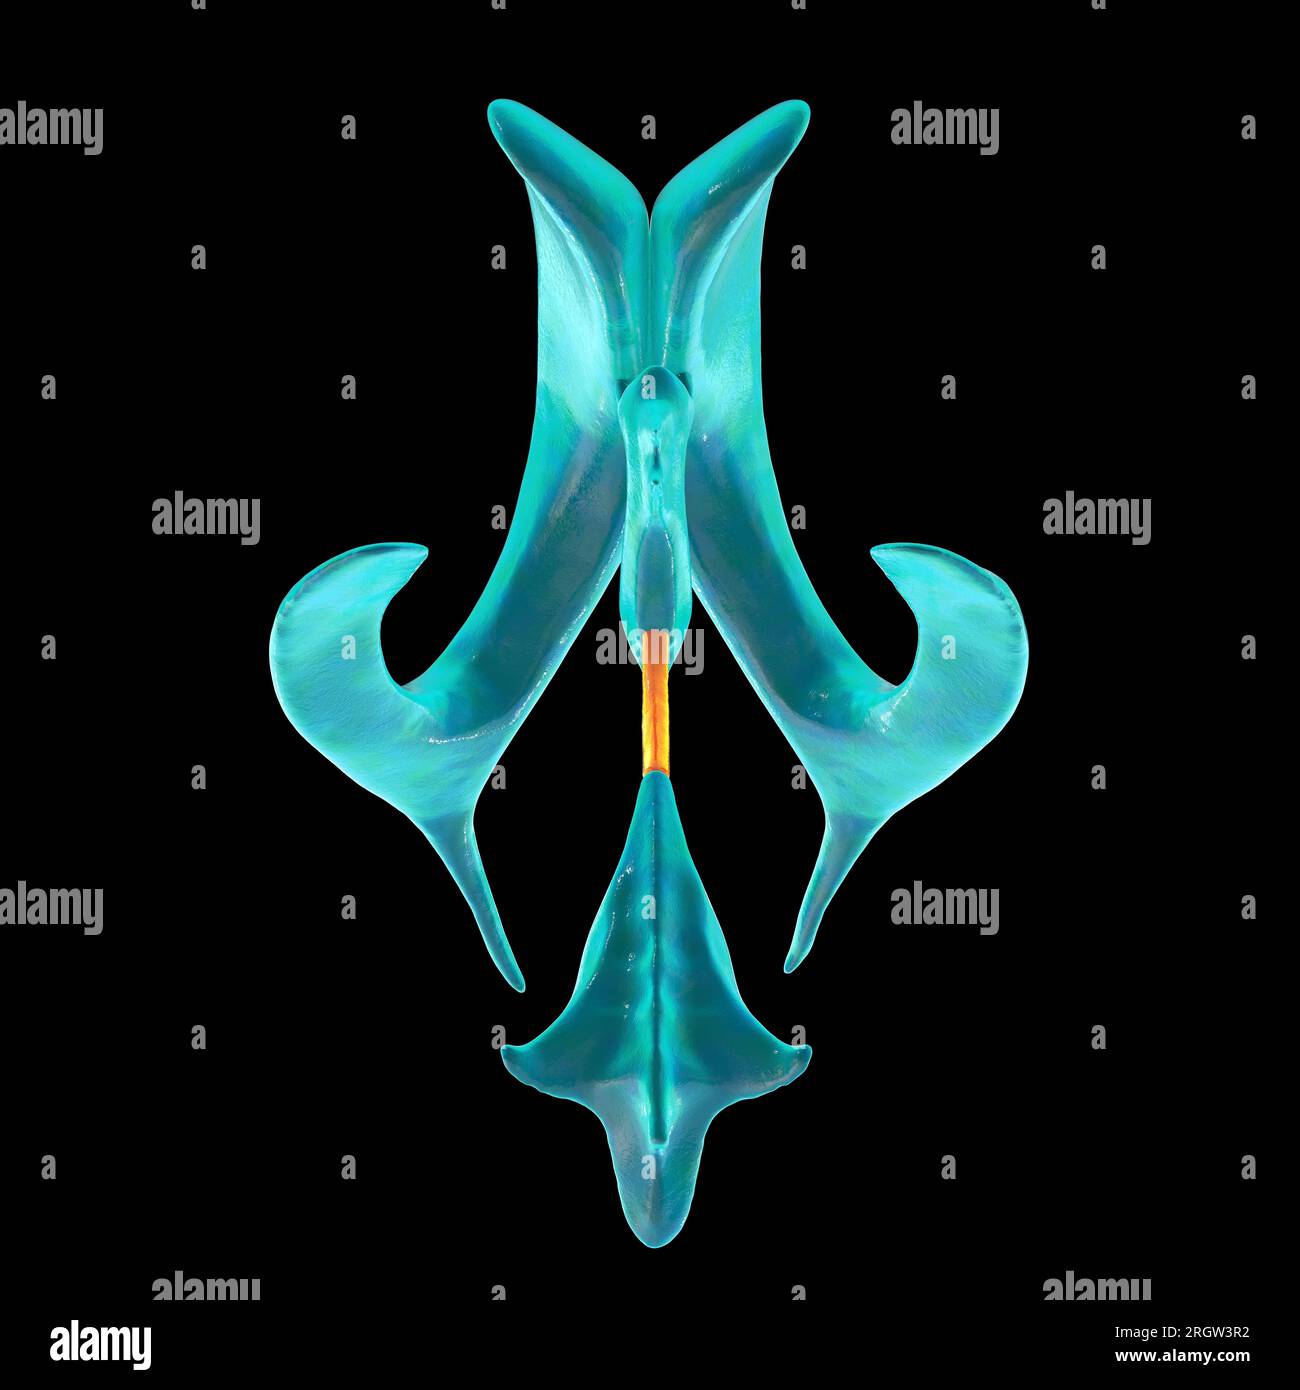

RF2T7NGWH–Ventrikel und zerebrales Aquädukt laterale Röntgenansicht 3D-Rendering-Illustration. Menschliches Gehirn und Ventrikelsystem Anatomie, Medizin, Gesundheitswesen, Scienc

RF2T7NGWK–Ventrikel und zerebraler Aquädukt lateral in Farben Röntgenbild-3D-Rendering-Illustration. Menschliches Gehirn und Ventrikelsystem Anatomie, medizinisch, gesund

RF2T7NGWR–Ventrikel und Hirn-Aquädukt-Röntgenprofil Nahansicht 3D-Rendering-Illustration mit Körperkonturen. Anatomie des menschlichen Gehirns und des Ventrikelsystems,

RF2T7NGWW–Ventrikel und zerebraler Aquädukt in Farben Röntgenprofil Nahansicht 3D-Rendering-Illustration. Anatomie des menschlichen Gehirns und des Ventrikelsystems, medizinisch,

RF2T030FH–Röntgenprofilansicht des Sylvius oder des zentralen Aquädukts des Gehirns 3D-Rendering-Illustration. Menschliche Körperanatomie, Medizin, Biologie, Wissenschaft, Neurowissenschaft,

RF2T6AR8J–3D-Rendering-Illustration für die Röntgenansicht des Gehirns oder des Sylvius aquädukt. Anatomie des menschlichen Gehirns und des Ventrikelsystems, Medizin, Gesundheitswesen, Biologie, Wissenschaft,

RF2T6AR96–Röntgenprofil des Gehirns oder sylvius aquädukt Nahansicht 3D-Rendering-Illustration mit Körperkonturen. Anatomie des menschlichen Gehirns und des Ventrikelsystems, med